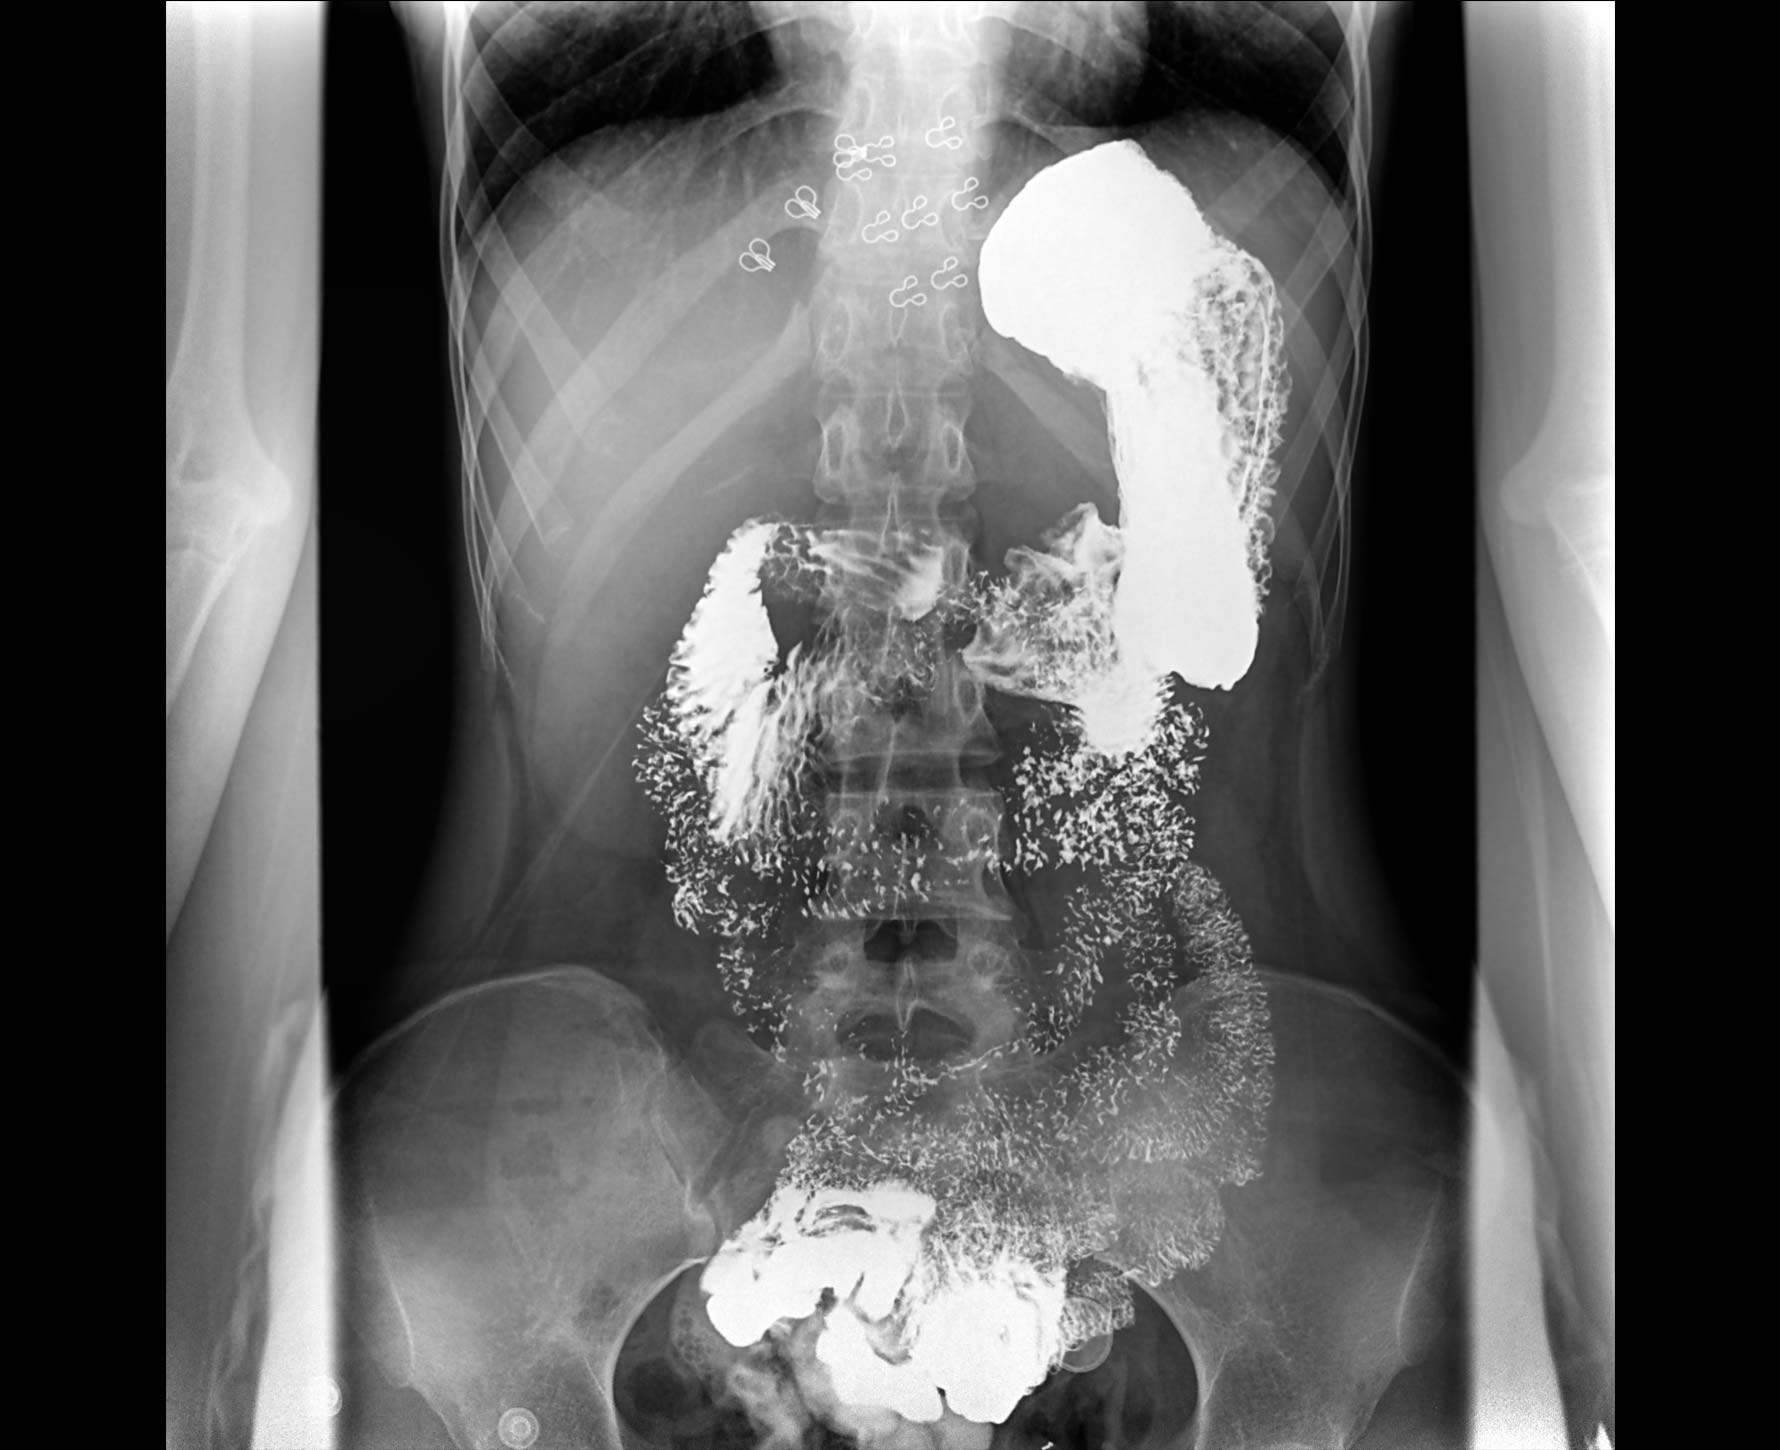

适用于各种普通

及特殊胃肠造影检查

• 特有视频保存与回放功能

对胃肠造影检查影像实时保存,多次回放以便确定病灶部位,患者确诊好帮手,减少漏诊。